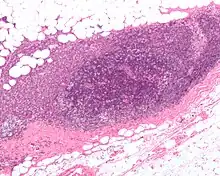

As seen on the image above the  breast is already affected with cancer

An illustration of breast cancer

• Histopathology. Breast cancer is usually classified primarily by its histological appearance. Most breast cancers are derived from the epithelium lining the ducts or lobules, and these cancers are classified as ductal or lobular carcinoma. Carcinoma in situ is growth of low-grade cancerous or precancerous cells within a particular tissue compartment such as the mammary duct without invasion of the surrounding tissue. In contrast, invasive carcinoma does not confine itself to the initial tissue compartment.[135]

• Grade. Grading compares the appearance of the breast cancer cells to the appearance of normal breast tissue. Normal cells in an organ like the breast become differentiated, meaning that they take on specific shapes and forms that reflect their function as part of that organ. Cancerous cells lose that differentiation. In cancer, the cells that would normally line up in an orderly way to make up the milk ducts become disorganized. Cell division becomes uncontrolled. Cell nuclei become less uniform. Pathologists describe cells as well differentiated (low grade), moderately differentiated (intermediate grade), and poorly differentiated (high grade) as the cells progressively lose the features seen in normal breast cells. Poorly differentiated cancers (the ones whose tissue is least like normal breast tissue) have a worse prognosis.